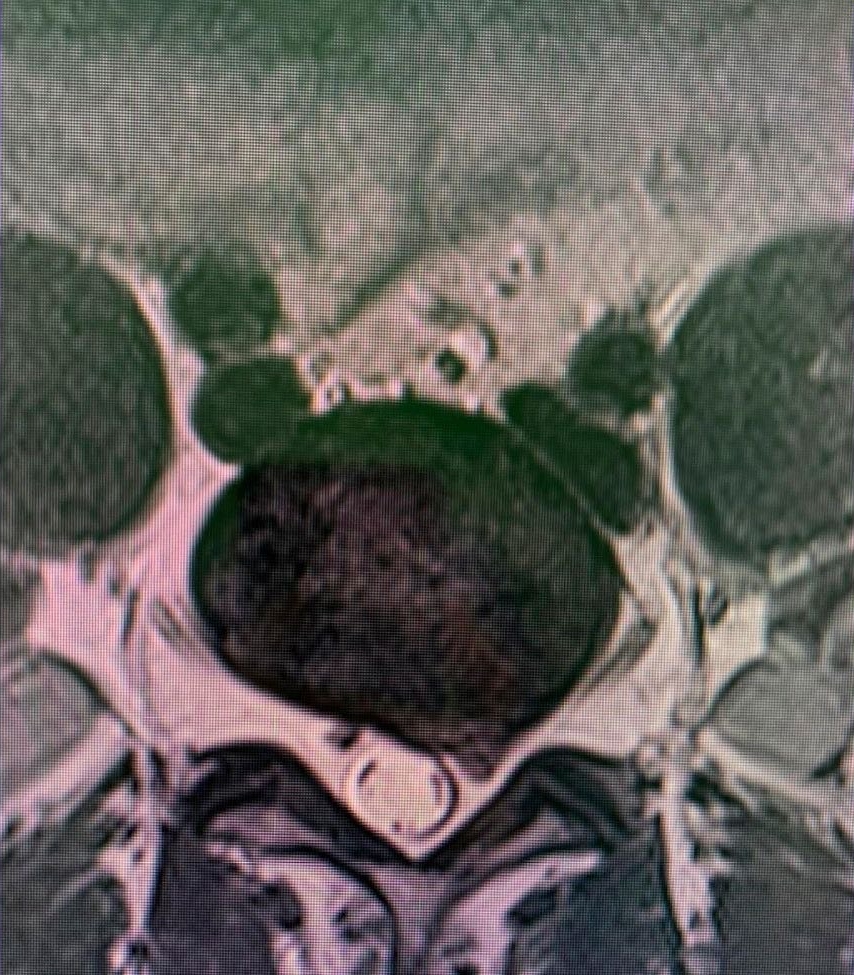

Un Glioma que causa efectos de compresión y «edema»(inflamación)

Un gran neurinoma acústico con compresión del tronco encefálico